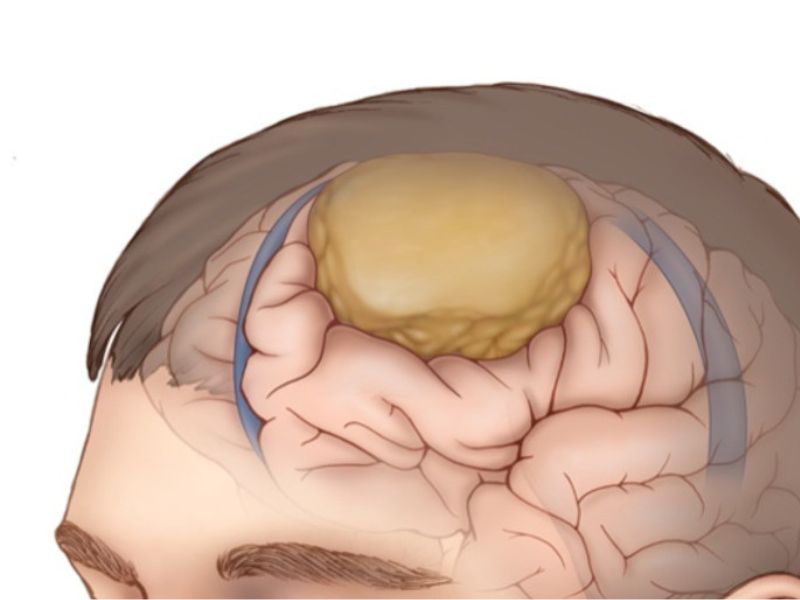

U màng não là một loại khối u nguyên phát của hệ thần kinh trung ương, bắt nguồn từ các tế bào nhung mao màng nhện trong màng não. Đây là dạng u phổ biến nhất của hệ thần kinh trung ương, chiếm khoảng 37,6% tổng số khối u nội sọ và gần 50% các khối u não lành tính. Màng nhện, nơi xuất phát của khối u đóng vai trò quan trọng trong việc bảo vệ não và duy trì hoạt động tối ưu của hệ thần kinh trung ương.

U màng não có thể gặp ở mọi vị trí trong hộp sọ, tuy nhiên các vị trí thường phát hiện u màng não bao gồm đỉnh đầu, hai bên thái dương và đôi khi trong ống sống (u màng cột sống hay u màng tủy).

U màng não là một loại khối u nguyên phát của hệ thần kinh trung ương